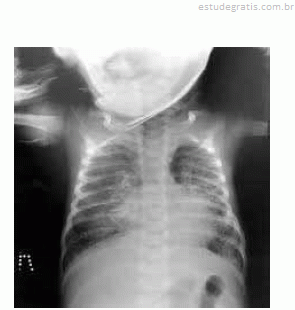

Em cada um dos itens de 57 a 59, é apresentado um caso clínico referente a doenças respiratórias na infância, seguido de uma assertiva a ser julgada.Um lactente de um mês de idade, nascido de parto vaginal, apresentava tosse seca havia uma semana. O exame físico do bebê constatou temperatura axilar de 37 ºC, hiperemia, edema e secreção serosa em conjuntivas, leve taquipneia e murmúrio vesicular rude com creptações disseminadas à ausculta pulmonar. Foi realizada radiografia do tórax, conforme ilustrado a seguir.

Nesse caso, o diagnóstico mais provável é pneumonia por Chlamydia trachomatis, e o tratamento do paciente deve ser realizado com azitromicina, na dose de 30 mg/kg por cinco dias.